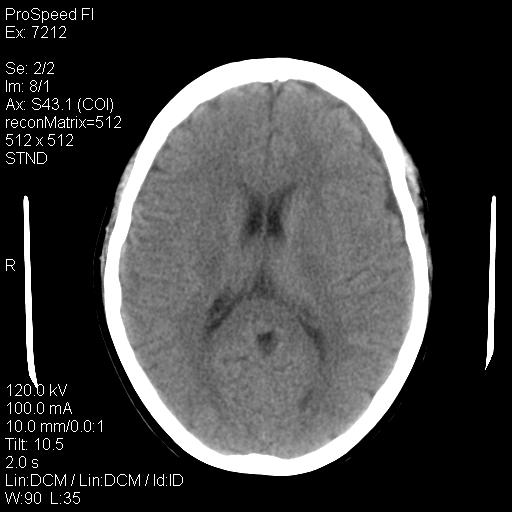

标题: CT18636:F 44Y,头痛三个月,左侧肢体麻木一周。临床诊断, [打印本页]

标题: CT18636:F 44Y,头痛三个月,左侧肢体麻木一周。临床诊断,

右额叶脑沟变浅,脑表面见新月形稍高密度影,考虑慢性硬膜下出血可能。

左侧额颞部慢性英模下血肿。

1)考虑左侧额部慢性硬膜下血肿(或硬膜下积液)。2)颅骨骨髓瘤不排除;建议行进一步检查。

1)考虑左侧额颞部及右侧额部慢性硬膜下血肿(或硬膜下积液)。2)颅骨骨髓瘤不排除;建议行进一步检查。

考虑左侧额部慢性硬膜下血肿(或硬膜下积液)。

1)右侧半卵圆中心腔隙性脑梗塞。2)考虑左侧额部慢性硬膜下血肿(或硬膜下积液)。3)颅骨骨髓瘤不排除;建议行进一步检查。